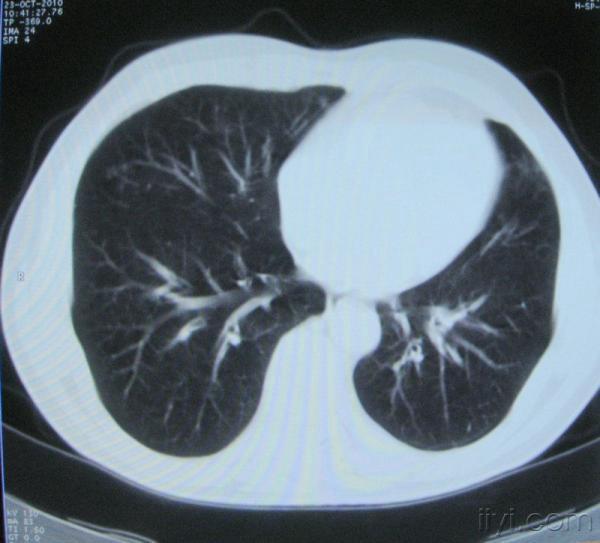

男。60岁,胸片示支气管炎治疗后复查CT。

你指那个肯定是淋巴结,中央系坏死,这很常见,特别在双侧腹股沟会经常看到。这个双侧腋窝及纵隔见多发小淋巴结征。

根据位置考虑应该是淋巴结,密度不均,是因为肿大的淋巴结中心液化坏死